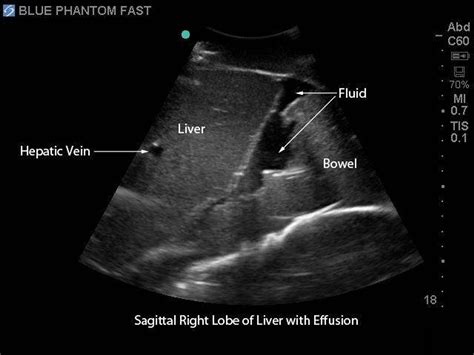

• Focused Abdominal Ultrasound: This evaluates the abdomen for free fluid, organomegaly, and other abnormalities.

• Abdominal Evaluation: It helps identify free fluid in the abdomen, organomegaly, and other abnormalities.

• Pathological Findings: Look for signs of pathology, such as fluid collections, organ abnormalities, and other conditions.